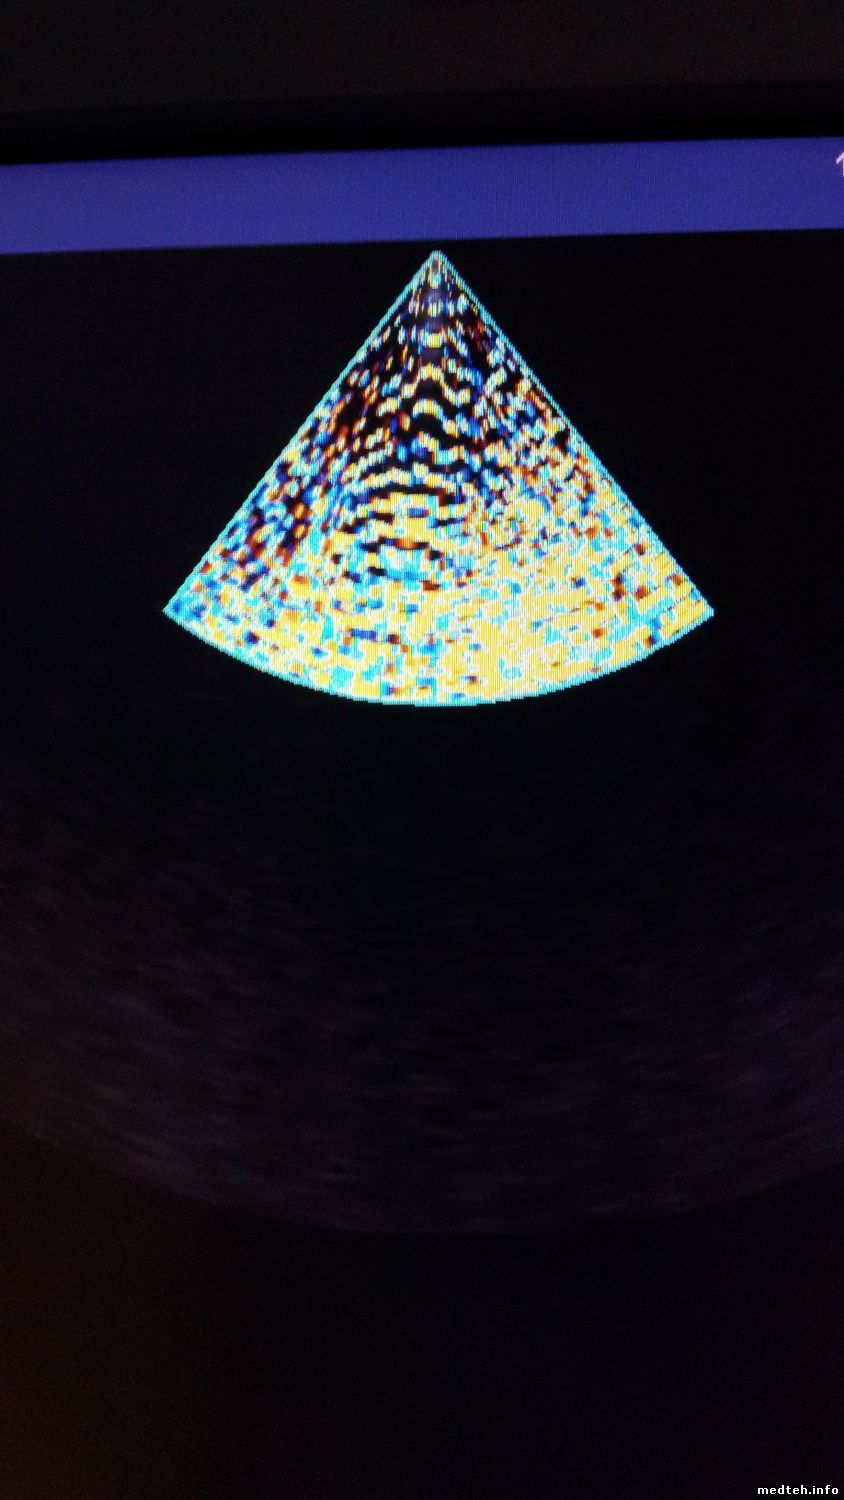

День добрый. Понимаю, что тема несколько устарела, но столкнулся с подобной проблемой как Senergy. Аппарат, siemens acuson x300, с периодически проявляющейся проблемой, фото прилагаю. Заземление проверенно, для пробы включал от ИБП с синусом на выходе, проблема все равно проявляется. В логах все чисто, нет ни одного FAIL, залез в блок питания что слева и осцилом проверил все напряжения в момент когда есть и нет этой проблемы, все напряжения в норме. Как говорит клиент, проблема проявляется и при смене датчика, но я лично этого не видел, так что остается "верить" словам клиента. Уже и не знаю, что еще можно проверить. Может кто чего подскажет

4305190.jpg (102.2 Kb) · 4516914.jpg (115.8 Kb)